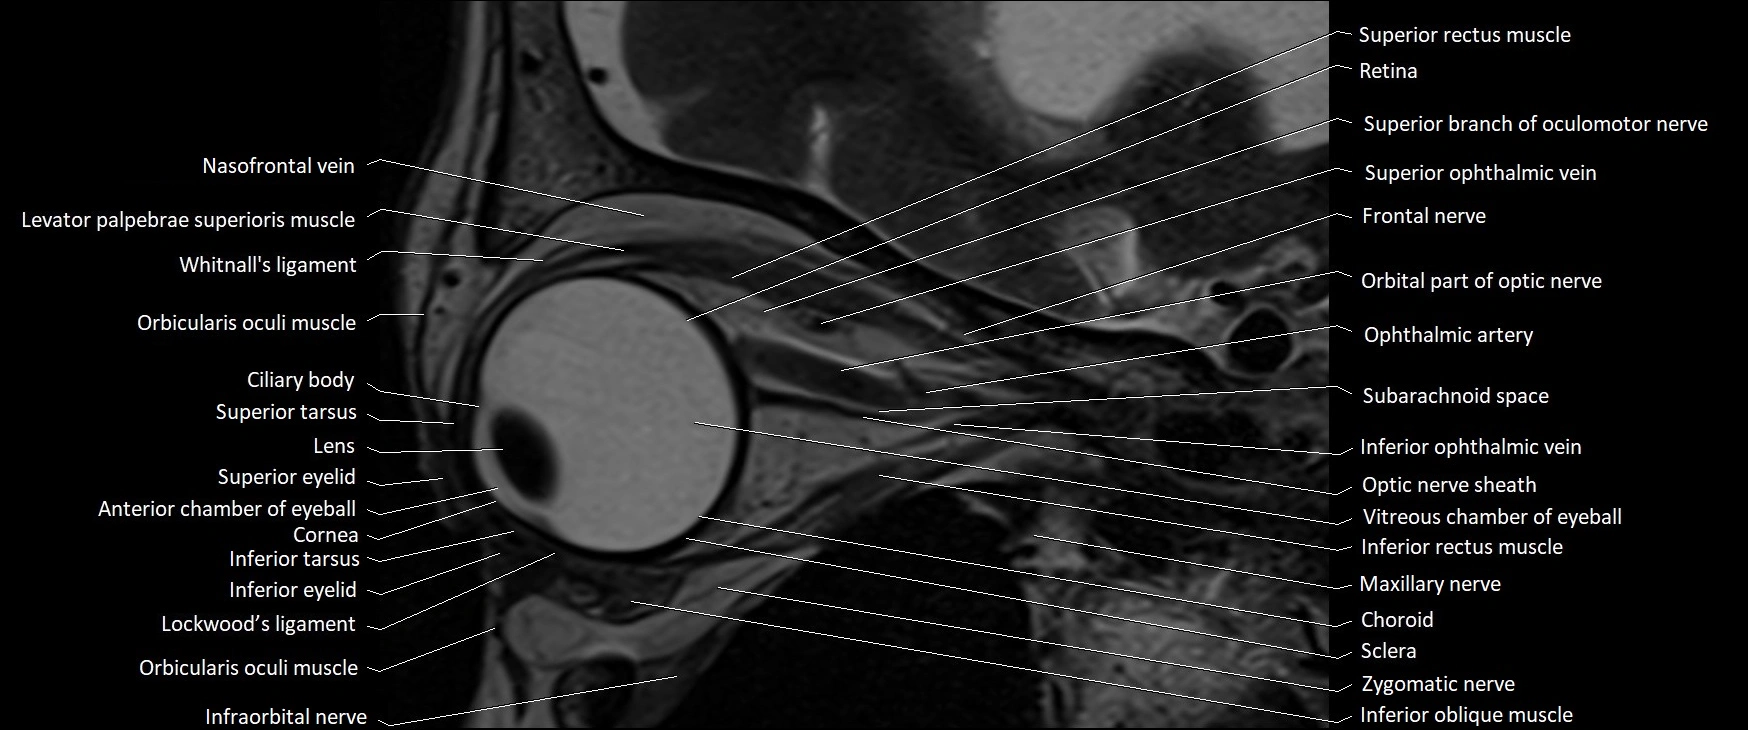

- Inferior ophthalmic vein

- Inferior rectus muscle

- Infraorbital nerve

- Intracranial part of optic nerve

- Lateral rectus muscle

- Levator palpebrae superioris muscle

- Lockwood’s ligament

- Maxillary nerve

- Nasofrontal vein

- Oculomotor nerve (Superior branch)

- Optic nerve sheath

- Orbicularis oculi muscle

- Orbital part of optic nerve

- Retina

- Sclera

- Subarachnoid space of optic nerve

- Superior eyelid

- Superior oblique muscle

- Superior ophthalmic vein

- Superior rectus muscle

- Superior tarsus

- Vitreous chamber of eyeball

- Whitnall's ligament

- Zygomatic nerve